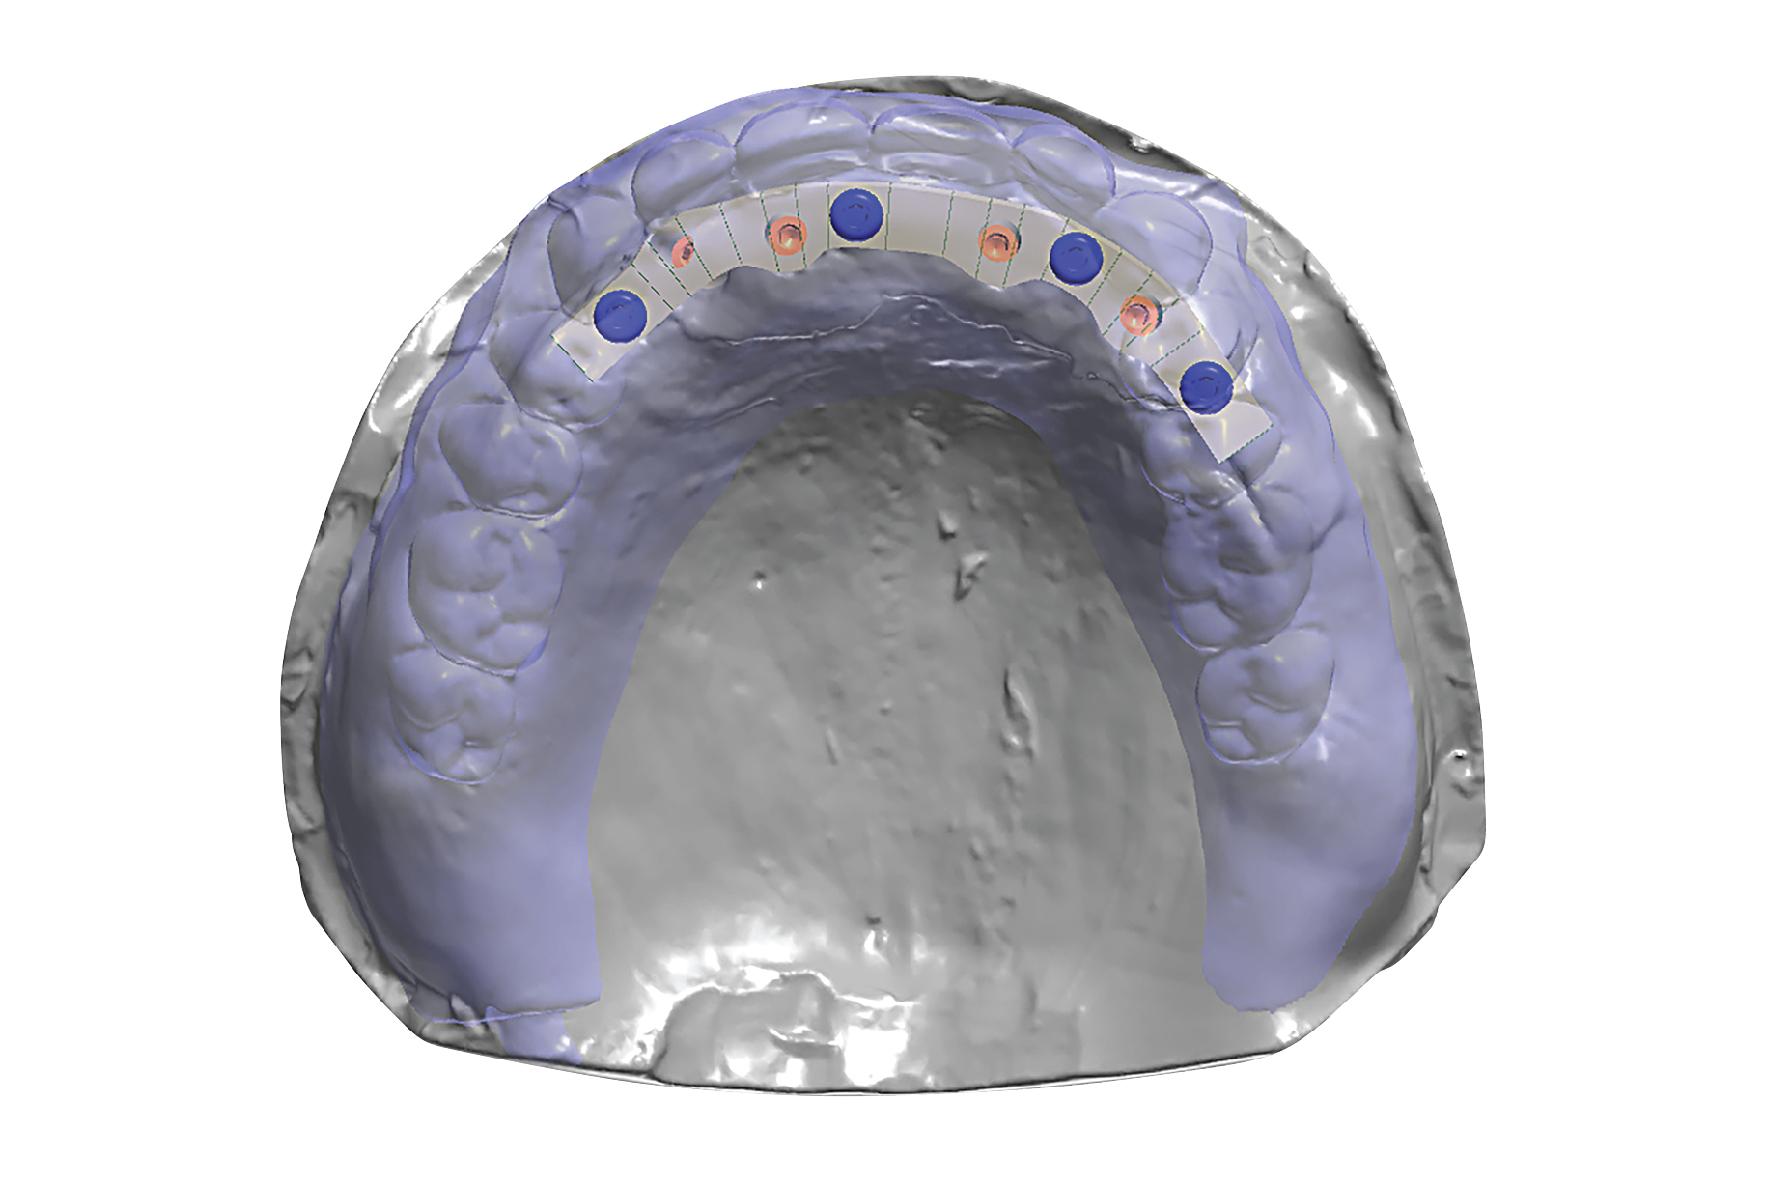

Our elegantly secure line offers a permanent solution for patients who are frustrated with their existing dentures. This is an implant-retained, removable prosthesis that performs, looks, and feels just like natural teeth. This restoration provides valuable benefits such as bone loss prevention and limited palatal coverage, significantly improving the ability to enjoy food. As a convenience to the patient, it is also easy to clean and maintain.

Supported by as few as two implants, this prosthesis offers a stabilized chewing surface and minimal risk of dislodging due to its milled titanium bar and attachments parallel to the occlusal table. Most patients obtain up to 90% of their function with this line! This is a great option for correcting non-parallel implants and compensates for significant implant divergence.

We know that proprioception and biting forces are hard to control with the loss of the periodontal ligament, so we engineered a solution to meet those demands. The elegantly secure line is manufactured to extremely high standards with extra hardened resin teeth, an internal tissue colored alloy frame for added support and dense injectable acrylics.